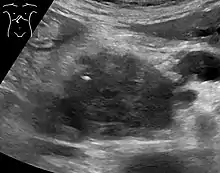

Medical imaging techniques, such as computed tomography (CT scan) and endoscopic ultrasound (EUS) are used both to confirm the diagnosis and to help decide whether the tumor can be surgically removed (its "resectability").[12] On contrast CT scan, pancreatic cancer typically shows a gradually increasing radiocontrast uptake, rather than a fast washout as seen in a normal pancreas or a delayed washout as seen in chronic pancreatitis.[50] Magnetic resonance imaging and positron emission tomography may also be used,[11] and magnetic resonance cholangiopancreatography may be useful in some cases.[30] Abdominal ultrasound is less sensitive and will miss small tumors, but can identify cancers that have spread to the liver and build-up of fluid in the peritoneal cavity (ascites).[12] It may be used for a quick and cheap first examination before other techniques.[51]